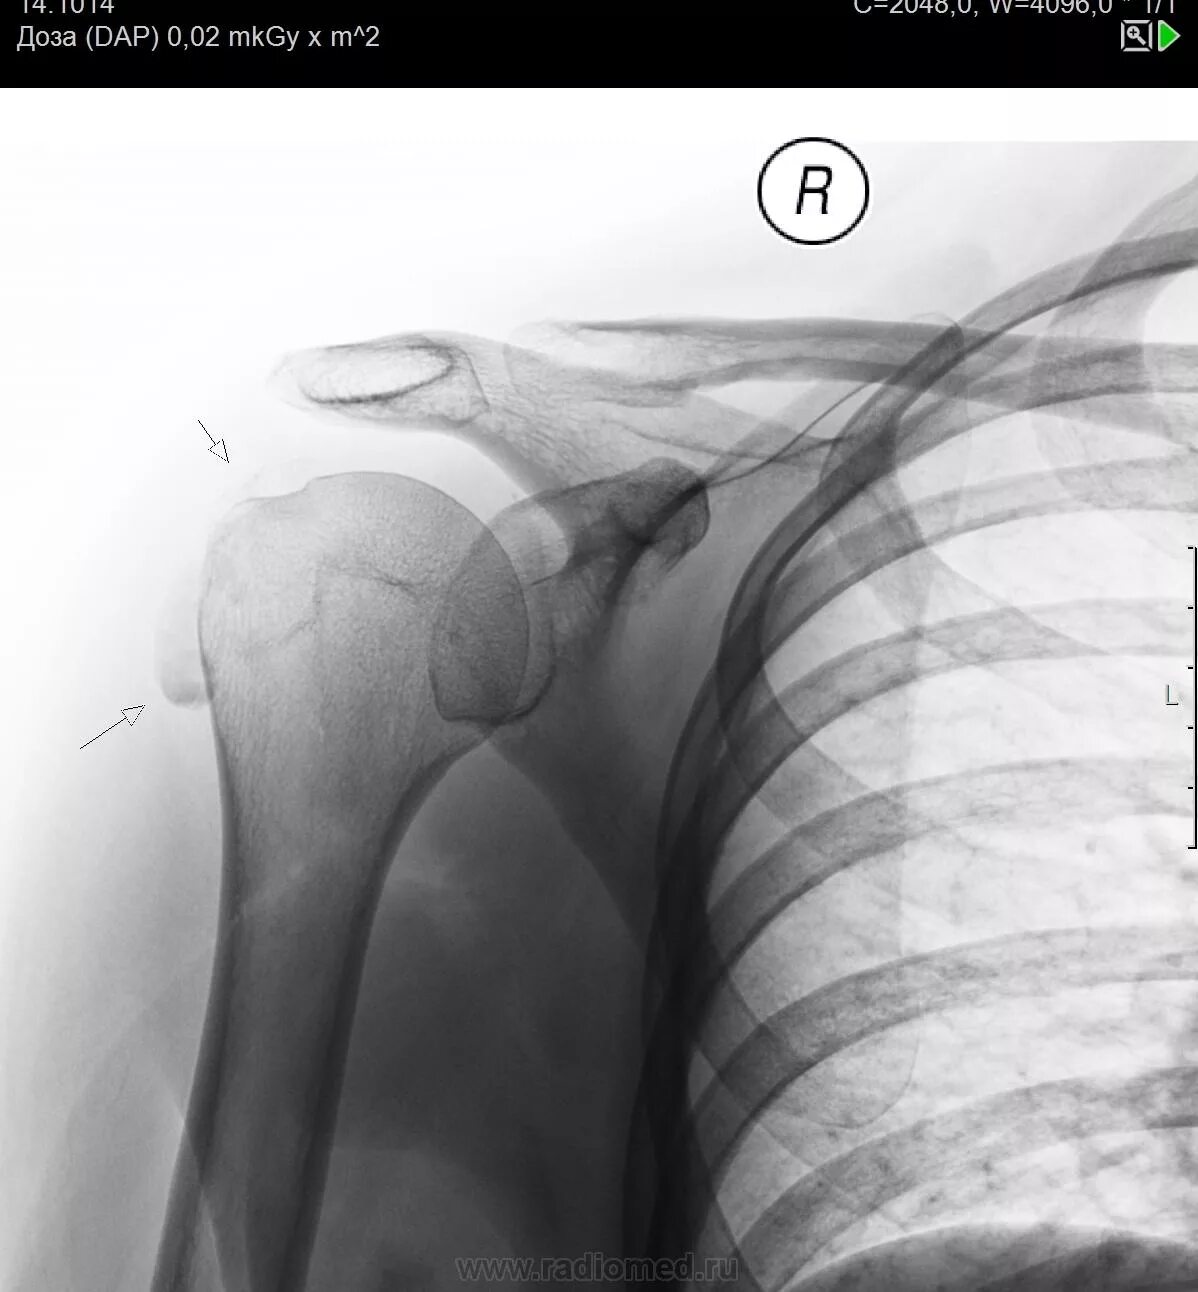

Обызвествление сухожилий мышц